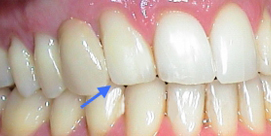

Spitzer Eckzahn vor Remodellation zum seitlichen Schneidezahn

Jetzt abgeflachter Eckzahn mit Zahnform eines seitlichen Schneidezahnes nach Remodellation (Odontoplatik)